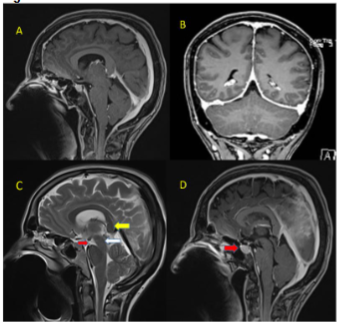

Her routine blood investigations including blood counts, liver and renal function tests were normal. Serum vitamin D and vitamin B12 levels were normal. CT brain and CT cerebral angiography was done in emergency to rule out any pituitary apoplexy, subarachnoid hemorrhage, vascular aneurysm, or vascular malformation, which was normal. Gadolinium-enhanced magnetic resonance imaging (MRI) showed bilateral subdural effusion, with diffuse smooth pachymeningeal enhancement (Figure 1). There was drooping of splenium of corpus callosum, sagging of the midbrain, reduced mammillo-pontine distance, and pituitary hyperaemia. MRI of the spine showed smooth dural enhancement of the cervical and thoracic region. No CSF leak was noted in the contrast images. MR venogram showed engorgement of the venous sinuses. The imaging findings were in countenance with SIH (Figure 2). Ultrasound of the thyroid showed mild diffuse thyroid enlargement, with mild increase in vascularity.

Previous reports have mentioned symptoms including visual blurring, tinnitus, changes in the sense of taste, limb paresthesias, poor memory, parkinsonism, chorea, cerebellar ataxia, change in personality, and galactorrhea due to traction of hypothalamus-pituitary system and brain stem. The MRI of our patient did not show any focal lesions in the brainstem, but it showed midbrain sagging and vertically oval distortion in shape of the midbrain. Bed rest and hydration improved the neurological signs. Our patient’s lab profile showed very low TSH with raised T3 and T4. She had positive anti TSH antibodies in very high titres along with raised anti TPO and antithyroglobulin antibodies. Anti-TSH Receptor antibodies are highly specific for Grave’s disease (GD) occurring in around in 90% of affected patients. It can be present in up to 20% Hashimoto’s thyroiditis (HT), and 10–75% of atrophic thyroiditis patients. Anti TPO antibodies are detected in 90–95% of patients with auto immune thyroid disease and can be positive in up to 80% of patients with GD. Thyroglobulin antibodies are relatively nonspecific and it can be present in up to 60–80% of HT and in 50–60% of GD patients. HT is usually associated with thyroid swelling and mostly presents with hypothyroidism. The presence of Anti-TSH Receptor antibodies and hyperthyroidism confirms the diagnosis of GD in our patient.